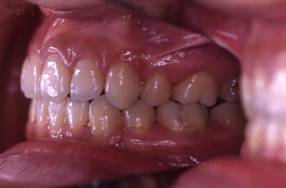

インビザGOによる矯正症例1 16歳男性

4か月後。犬歯が外側に出てきました

治療終了後10か月